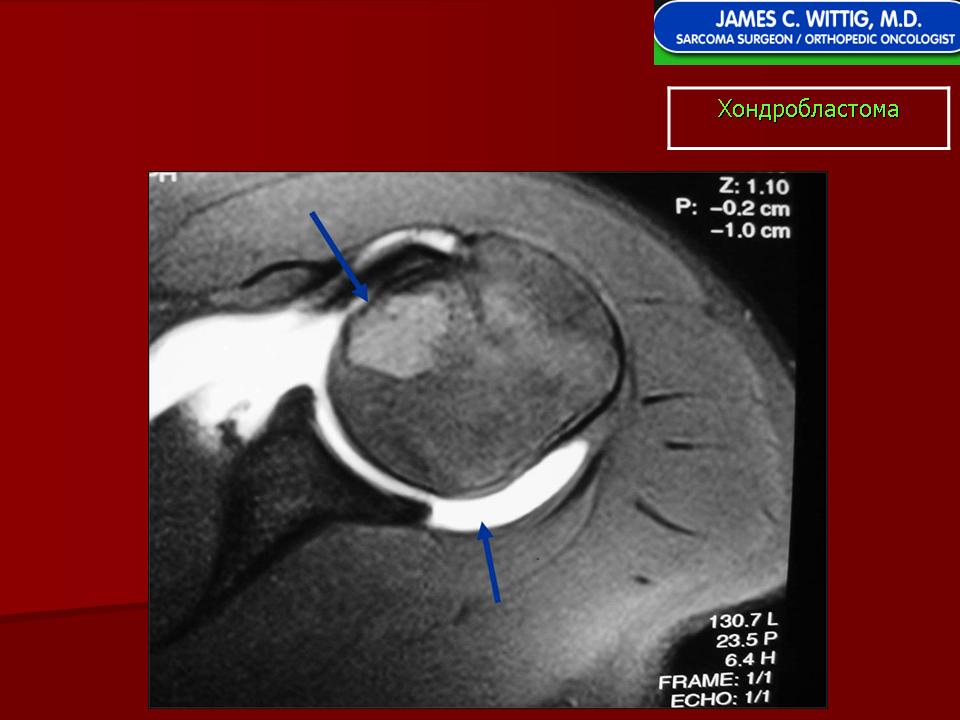

Хондробластома — это редкая доброкачественная опухоль, локализующаяся, главным образом, в эпифизе и отличающаяся своеобразным клеточным составом. Ткань новообразования представлена овальными, округлыми и веретеновидными клетками, напоминающими незрелые хондроциты (хондробласты). Зрелый гиалиновый хрящ определяется лишь в некоторых опухолях. Возраст больных варьирует. Мужчины поражаются в два раза чаше женщин. Пациенты предъявляют жалобы на боли в течение нескольких месяцев или лет, у некоторых больных определяются внутрисуставной выпот, припухлость и ограничение движений. Наиболее типичная локализация опухоли — проксимальные эпифизы плечевой и большеберцовой костей, а также дистальный эпифиз бедренной кости. У 20 % больных опухоль развивается в плоских или коротких трубчатых костях, преимущественно в пяточной и таранной. Изредка поражаются кости лицевого черепа, в том числе височная. В большинстве случаев новообразование выходит за пределы эпифиза и распространяется на метафиз. На фоне остеолиза обнаруживаются рассеянные участки обызвествления в виде пунктирных линий, а также разреженный трабекулярный рисунок. Хондробластома, как правило, не выходит за пределы кости, но изредка проникает в полость сустава. В процессе роста опухоли иногда возникает вторичная аневризматическая костная киста.

Рентгенологическая картина. Хондробластома выглядит как небольшой, от 3 до 6 см литический очаг, центрально или эксцентрично расположенный, с четкими контурами, занимающий около половины площади эпифизарной зоны. Хондробластома плоских костей и мелких трубчатых костей больших размеров, может сопровождаться припухлостью мягких тканей, вздутием кости и периостальной реакцией. Распространение процесса на метафизарную зону встречается часто.

Хондробластома — это редкая доброкачественная опухоль, локализующаяся, главным образом, в диафизах и отличающаяся своеобразным клеточным составом. Ткань новообразования представлена овальными, округлыми и веретеновидными клетками, напоминающими незрелые хондроциты (хондробласты). Зрелый гиалиновый хрящ определяется лишь в некоторых опухолях. Возраст больных варьирует от 3 до 72 лет. Мужчины поражаются в два раза чаше женщин. Пациенты предъявляют жалобы на боли в течение нескольких месяцев или лет, у некоторых больных определяются внутрисуставной выпот, припухлость и ограничение движений. Наиболее типичная локализация опухоли — проксимальные эпифизы плечевой и большеберцовой костей, а также дистальный эпифиз бедренной кости. У 20 % больных опухоль развивается в плоских или коротких трубчатых костях, преимущественно в пяточной и таранной. Изредка поражаются кости лицевого черепа, в том числе височная. При рентгенологическом исследовании видна типичная картина злокачественной опухоли остеолитического типа. В большинстве случаев новообразование выходит за пределы эпифиза и распространяется на метафиз. На фоне остеолиза обнаруживаются рассеянные участки обызвествления в виде пунктирных линий, а также разреженный трабекулярный рисунок. Хондробластома, как правило, не выходит за пределы кости, но изредка проникает в полость сустава. В процессе роста опухоли иногда возникает вторичная аневризматическая костная киста. Хондробластома — это доброкачественная опухоль, поэтому для ее лечения используется кюретаж с последующей костной пластикой. У некоторых больных в течение 3 лет после этого возникает рецидив, для лечения которого также используется кюретаж или же резекция опухоли. Примерно 1 % хондробластом отличается агрессивным местным ростом и метастазирует в легкие, причем метастазы могут выявляться спустя многие годы после обнаружения первичного узла. Некоторые хондробластомы прорастают в окружающие мягкие ткани, но при этом не метастазируют. Описаны случаи малигнизации этого новообразования после лучевой терапии с формированием фибро-или остеосаркомы. Макроскопический вид хондробластомы варьирует. Обычно опухоль состоит из зернистой ткани желтовато-серого или буровато-серого цвета, в которой определяются кровоизлияния и аневризматические кисты. Видны также голубовато-серые участки, соответствующие хондроидному матриксу. Точечные желтоватые вкрапления соответствуют очагам обызвествления или реактивного остеогенеза. По периферии опухоли определяется поясок склерозированной костной ткани. Микроскопическая картина зависит, главным образом, от количества хондроидного матрикса, продуцируемого опухолевыми клетками, а также от распространенности некроза, наличия аневризматических кист. Обращает на себя внимание клеточный полиморфизм. Наибольшее число клеток составляют хонлробласты с четкими контурами, в которых определяются округлые или овальные ядра, окруженные зоной просветления. Ядра клеток расщепленные, с глубокими инвагинациями и вдавлениями. Ядерный хроматин выглядит мелкораспыленным или в виде скоплений неправильной формы. Число фигур митоза в опухоли обычно невелико, и они определяются только в 75 % случаев. Лишь изредка это число превышает 4 на 10 полей зрения при большом увеличении микроскопа. Атипичный митоз не встречается. Клеточный атипизм обнаруживается лишь у 20—30 % хондробластом. Обычно это крупные неправильной формы клетки с гиперхромными ядрами. По-видимому, их наличие не является неблагоприятным прогностическим признаком. В некоторых участках границы между хондробластами неотчетливые, и общая картина приобретает вид синцития. Наряду с округлыми элементами в опухоли встречаются и веретеновидные клетки, которые образуют гнездные скопления или же равномерно вкраплены между типичными клетками. Встречаются также многоядерные клетки, часть которых очень похожи на крупные остеокласты. Все вышеописанные клетки дают положительную реакцию на SlOO-протеин, нейронспецифическую энолазу и виментин.